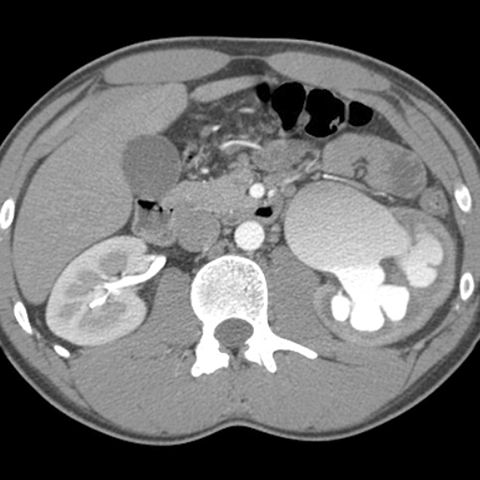

Hydronephrotic left kidney, axial CT [2 of 4]